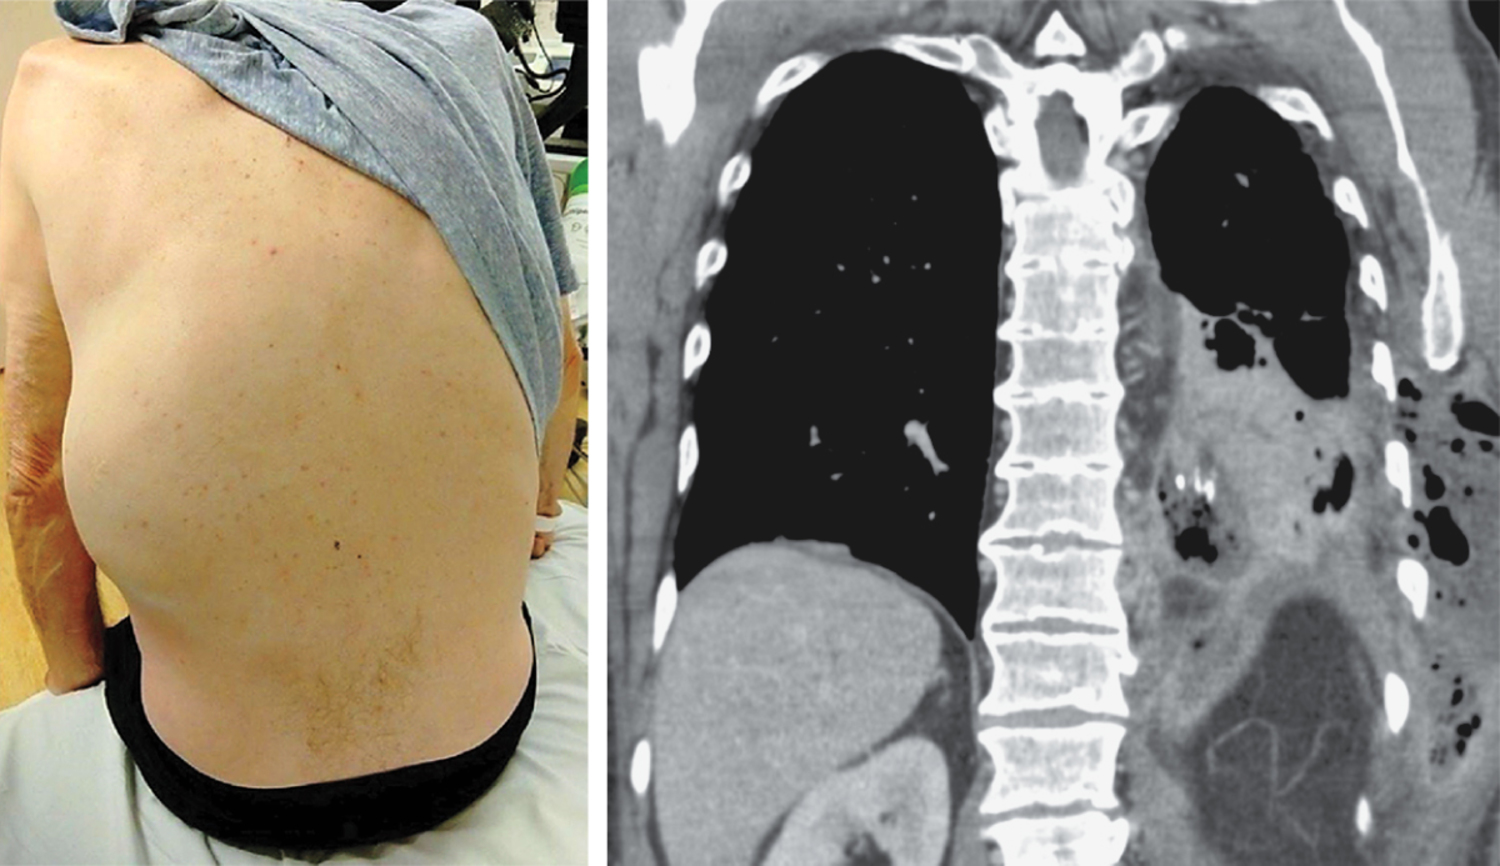

A 66-year-old man with chronic obstructive pulmonary disease presented to the emergency department with a 2-week history of shortness of breath and cough and 5 days of left flank pain. Two days before presentation, he had noted the appearance and rapid expansion of a mass on his left side. Computed tomography of the chest is shown. What is the underlying etiology?

诊断为脓胸穿通胸腔(empyema necessitans)——这是脓胸的一种罕见并发症,指感染从壁层胸膜蔓延至胸壁。随后对患者进行了胸壁肿块的切开引流术。胸膜液培养结果显示中间链球菌(Streptococcus intermedius)生长。患者完成了长期的抗生素治疗疗程。